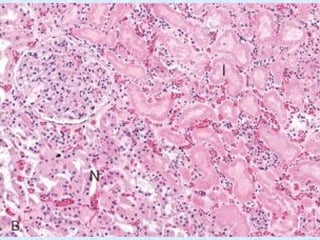

Figure 1-19 Coagulative and liquefactive necrosis. A, Kidney infarct

exhibiting coagulative necrosis, with loss of nuclei and clumping of

cytoplasm but with preservation of basic outlines of glomerular and

tubular architecture. B, A focus of liquefactive necrosis in the kidney

caused by fungal infection. The focus is filled with white cells and cellular

debris, creating a renal abscess that obliterates the normal architecture.

• #19 Microscopically, the renal cortex has undergone anoxic injury at the left so that the cells appear pale and ghost-like. There is a hemorrhagic zone in the middle where the cells are dying or have not quite died, and then normal renal parenchyma at the far right. This is an example of coagulative necrosis.

• #20 FIGURE 1-11  Coagulative necrosis: B, Microscopic view of the edge of the infarct, with normal kidney (N) and necrotic cells in the infarct (I) showing preserved cellular outlines with loss of nuclei and an inflammatory infiltrate (which is difficult to discern at this magnification).